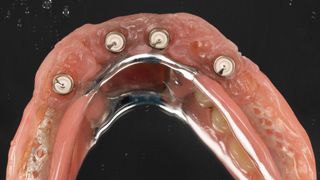

7a. 7b. Post-operative view of the complete removable prosthesis immediately secured to the mini implants with Optiloc connectors.

The post-operative instructions given were a soft diet for 15 days with no removal of the prosthesis during this initial healing phase. The patient was prescribed level 1 painkillers and mouthwash).

7a

7b